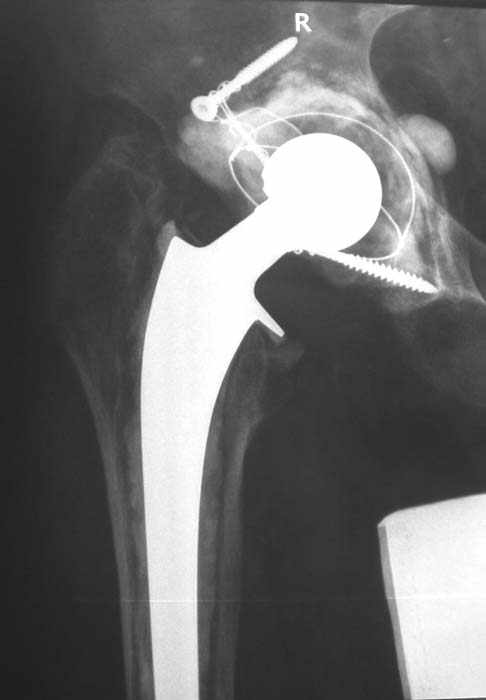

Мужчина, 45 лет. 6 мес. назад перенес тотальное эндопротезирование правого тазобедренного сустава по поводу ложного сустава шейки бедра.

Характер реконструкции вертлужной впадины не известен. Через 3 мес. после операции отметил щелчки и хруст при движениях в области эндопротеза. В анамнезе туберкулез легких. Сейчас, по заключению фтизиатра, в легких активного процесса нет. Местного воспаления нет.Предполагается нестабильность чашки в связи с бактериальным воспалением. Планируется удаление чашки и цемента, пластика дна измельченными аутотрансплантами и гидроксилапатитной керамикой, затем кольцо Мюллер, цементная чашка.

Смущает и ножка - зона просветления вокруг мантии. Предложения по тактике?

прямо скажем, очень загадочная конструкция с проволокой и винтами. :) На основании чего Вы подозреваете септическую нестабильность? Каковы результаты анализов? Согласен с доктором - нужно сделать пункцию. Есть ли снимки до и сразу после операции? Знаете ли Вы диаметр головки,какой будет внутренний диаметр Вашей чашки? Известно ли, чей протез? Может есть смысл найти автора работы и узнать о подробностях установки протеза?